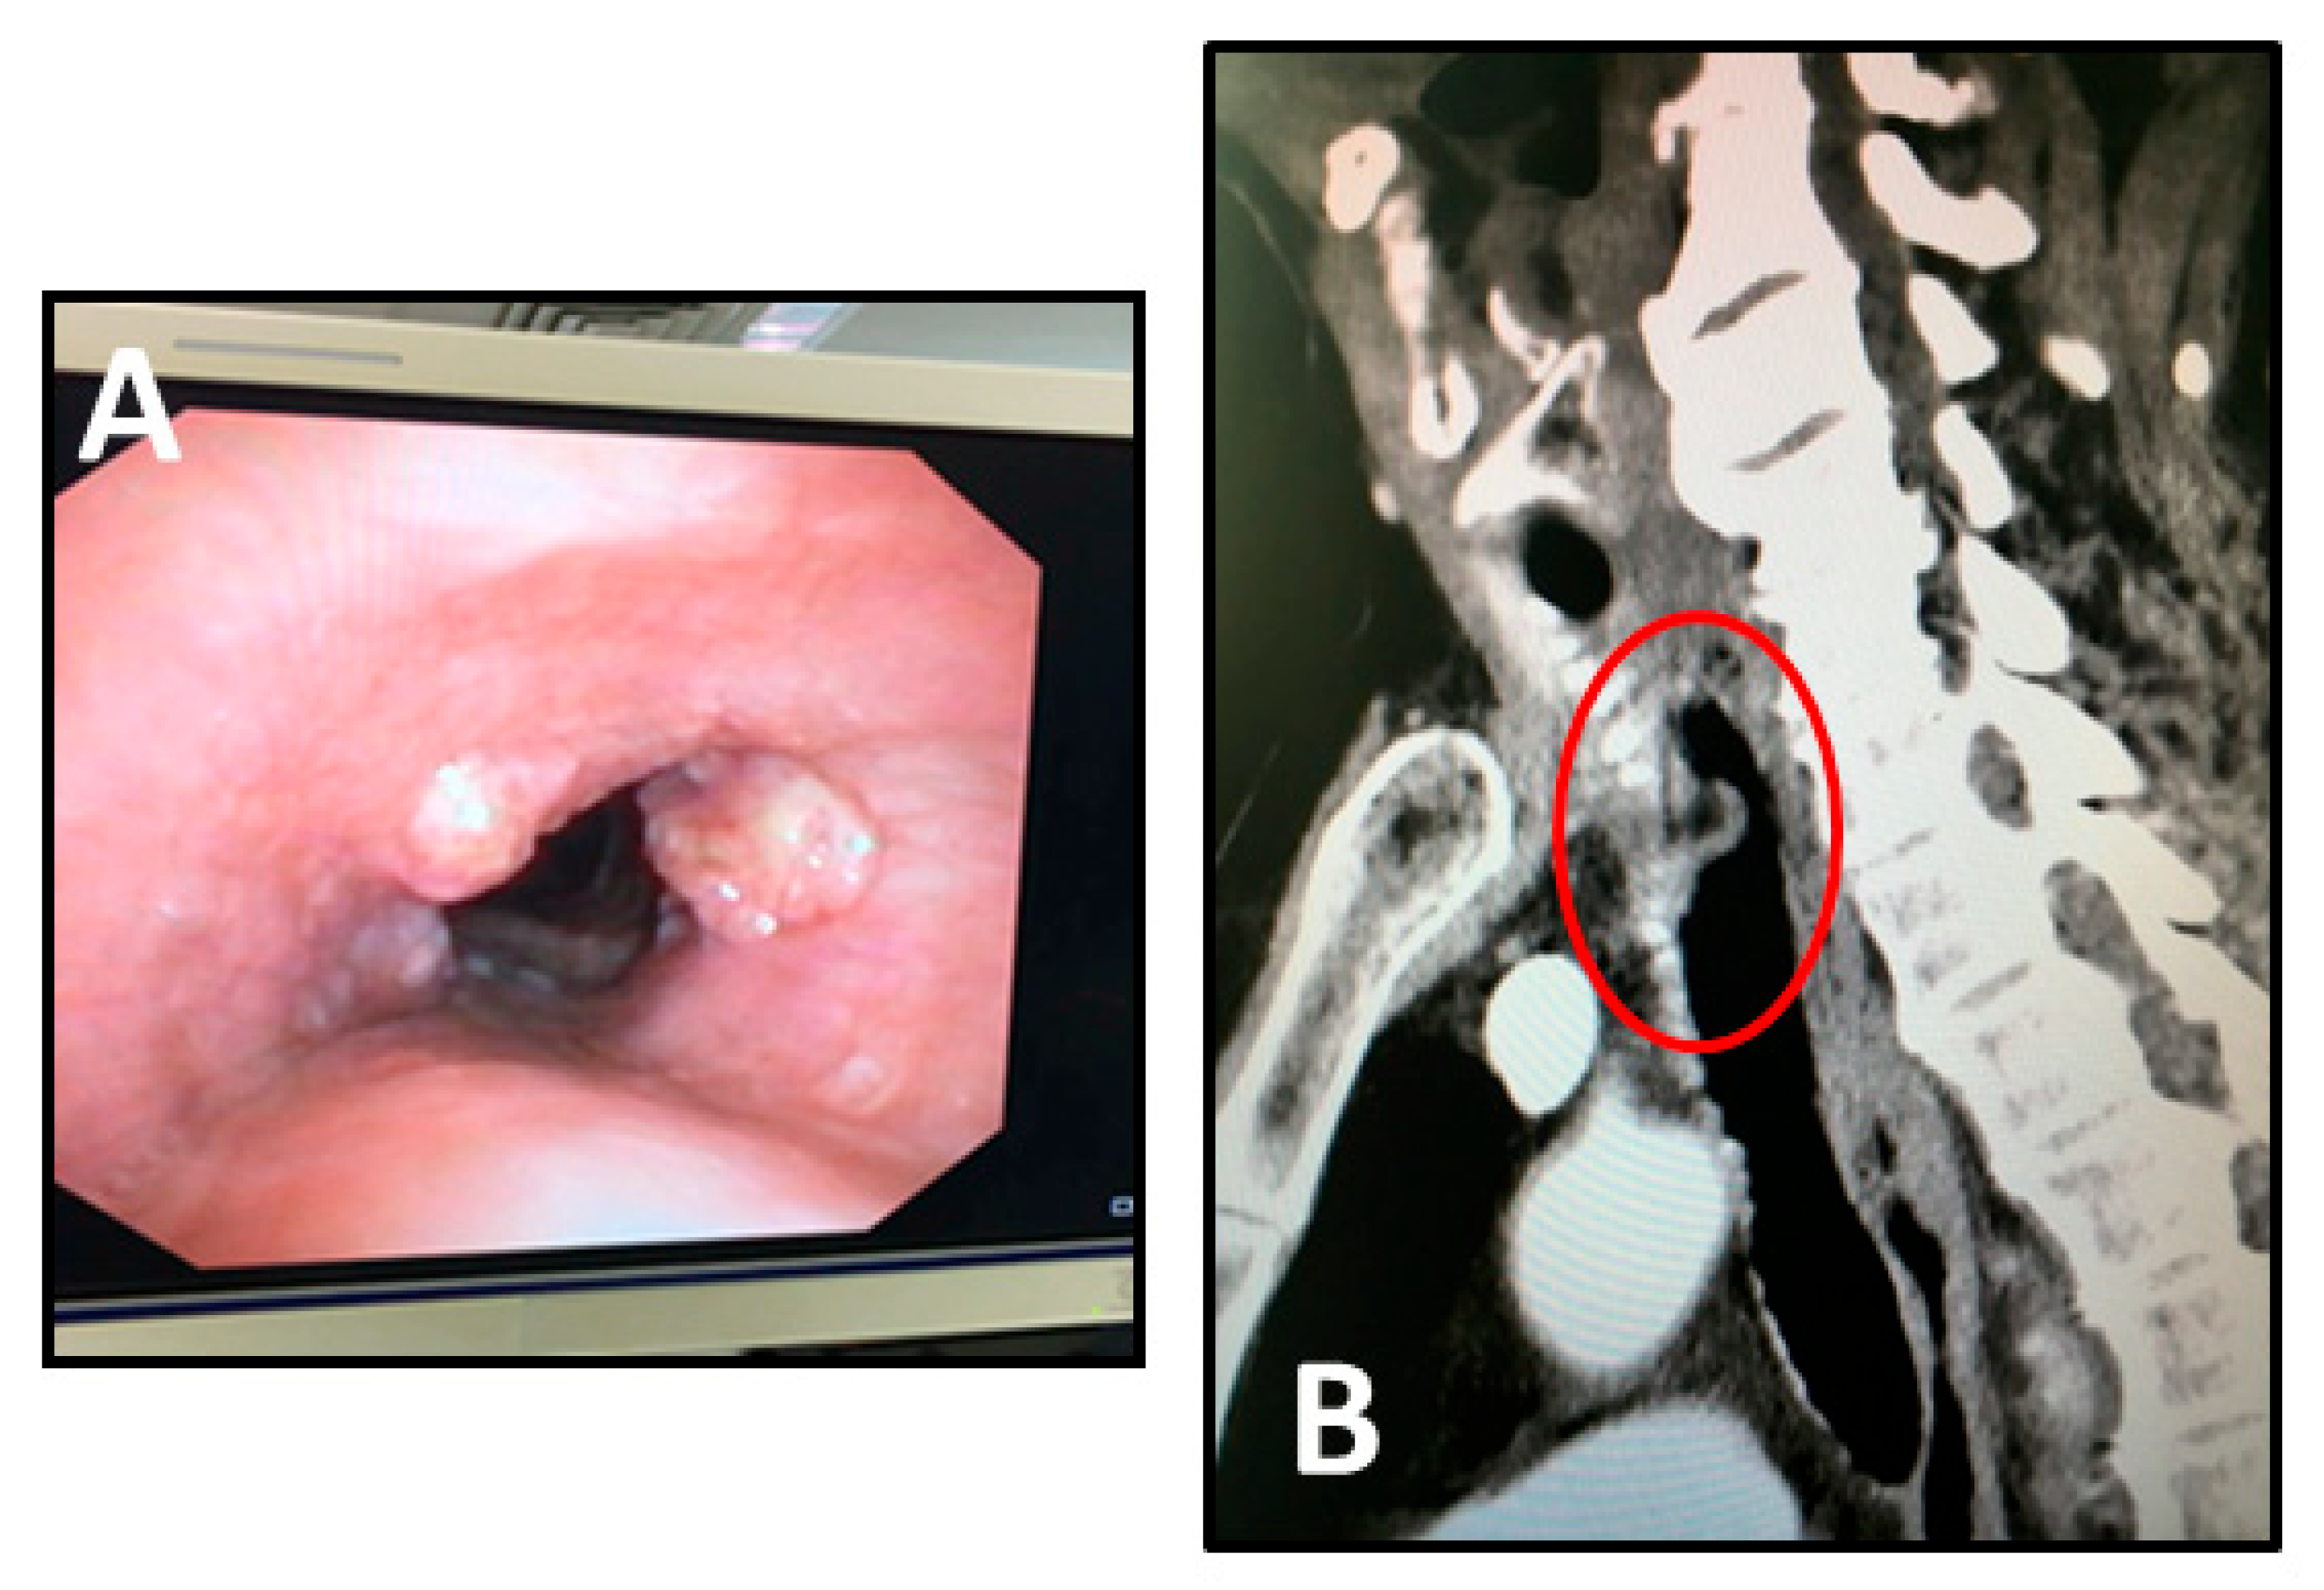

The case was discussed at the local multidisciplinary tumour board (MTB) and, considering the length and thickness extension of the tumour, induction chemotherapy was indicated. After two cycles of Cisplatin and Fluorouracil we observed a partial response with a reduction in the thickness of the tumour at the bronchoscopy (Figure 1A) and computed tomography (CT) scan imaging (Figure 1B). The patient was once more discussed at the MTB and scheduled for surgical treatment.

Figure 1. Preoperative evaluation after induction chemotherapy: (A) bronchoscopic view of middle tracheal cancer; (B) chest CT scan showing a mass (round), measuring about 30 mm along the longitudinal axis of the trachea, involving the anterior wall of the mediastinal trachea.